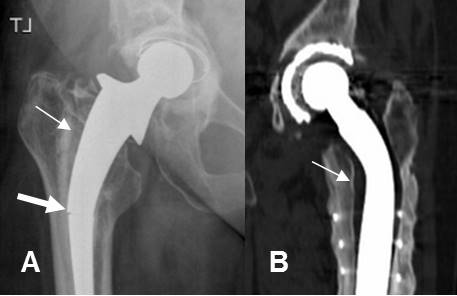

Fig 127. Aflojamiento.

A: Rx AP de cadera. Aflojamiento de la prótesis, con un espacio mayor de 2 mm. Adicionalmente hay fractura en el tercio medio del vástago. (Flecha gruesa).

B: TAC reconstrucción coronal. Otro caso con aflojamiento de la prótesis.